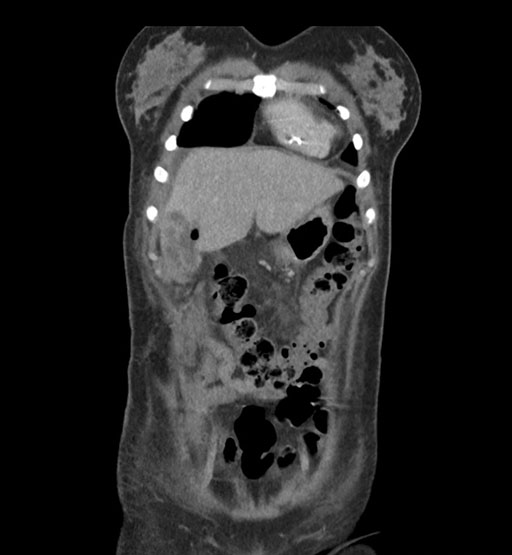

Axial Arterial

Coronal Arterial

Imaging analysis

Based on initial findings, which issue(s) would you be most concerned about?